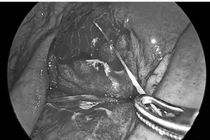

di-vat-2.jpg

Hình ảnh X-quang dị vật trước khi can thiệp và sau khi được đưa ra khỏi vùng hố thái dương sau 13 năm - Ảnh BVCC